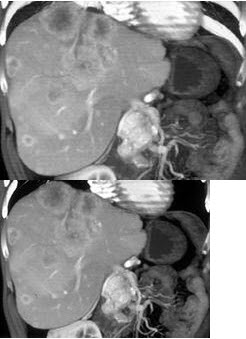

男,48岁,胃癌术后1年,未化疗,CT检查如图所示,最可能诊断为( )

A:肝癌

B:肝转移癌

C:肝血管瘤

D:肝脓肿

E:肝囊肿